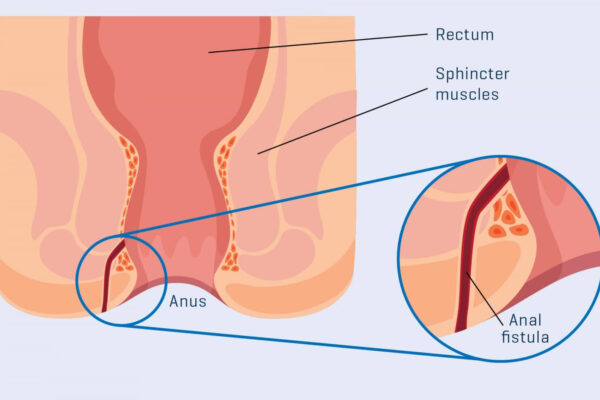

Overview

Package includes:

Days in hospital : 2 to 3 Days (For patient and one attendant)

Days in hotel : 7 Days (For patient and one attendant)

Room type in hospital : Shared

Room type in hotel : Private

Hotel category: Standard

Value added benefits of the Anal Fitsula:

Ø Doctor consultation charges

Ø Lab tests and diagnostic charges

Ø Room charges inside hospital during the procedure

Ø Surgeon Fee

Ø Nursing charges

Ø Hospital surgery suite charges

Ø Anesthesia charges

Ø Routine medicines and routine consumables (bandages, dressings etc.)

Ø Food and Beverages inside hospital stay for patient and one attendant.

Extra benefits:

ü Interpreter

ü Visa assistance

Ø Site tourism of the city

Ø Follow up with the doctor

Ø Airport pick up and drop

Ø Free online consultation with the doctor

Ø Priority appointments with the doctor

Ø Room upgrade from sharing to private